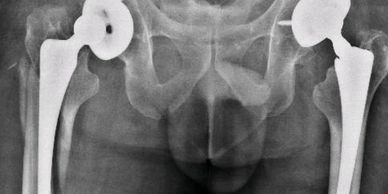

Paciente de 52 años, con artrosis bilateral de cadera. Se realizó una artroplastía total de cadera bilateral en un tiempo.